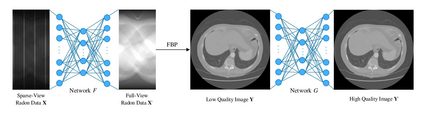

Sparse-view computed tomography (CT) is known as a widely used approach to reduce radiation dose while accelerating imaging through lowered projection views and correlated calculations. However, its severe imaging noise and streaking artifacts turn out to be a major issue in the low dose protocol. In this paper, we propose a dual-domain deep learning-based method that breaks through the limitations of currently prevailing algorithms that merely process single image slices. Since the scanned object usually contains a high degree of spatial continuity, the obtained consecutive imaging slices embody rich information that is largely unexplored. Therefore, we establish a cascade model named LS-AAE which aims to tackle the above problem. In addition, in order to adapt to the social trend of lightweight medical care, our model adopts the inverted residual with linear bottleneck in the module design to make it mobile and lightweight (reduce model parameters to one-eighth of its original) without sacrificing its performance. In our experiments, sparse sampling is conducted at intervals of 4{\deg}, 8{\deg} and 16{\deg}, which appears to be a challenging sparsity that few scholars have attempted before. Nevertheless, our method still exhibits its robustness and achieves the state-of-the-art performance by reaching the PSNR of 40.305 and the SSIM of 0.948, while ensuring high model mobility. Particularly, it still exceeds other current methods when the sampling rate is one-fourth of them, thereby demonstrating its remarkable superiority.